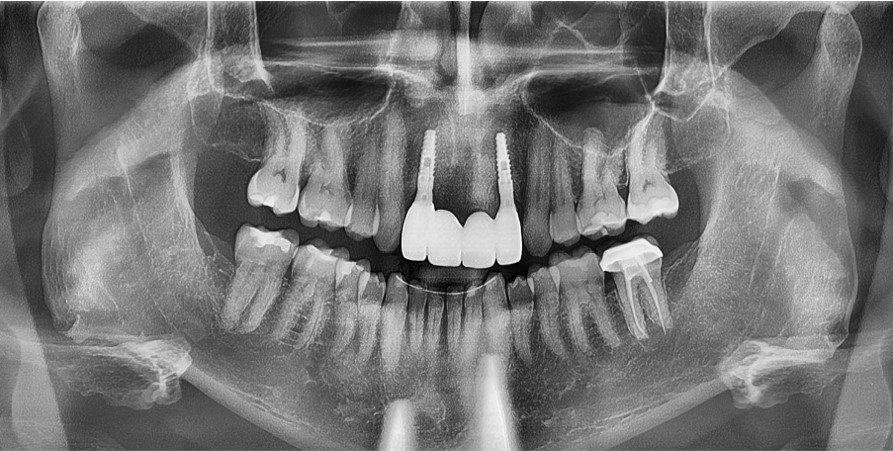

Many years ago, this patient had trauma and he had developed an abscess requiring the removal of his front four teeth. Using fully guided implant surgery we were able to rebuild his smile with bone grafting and implants. We love to see our patients smile!